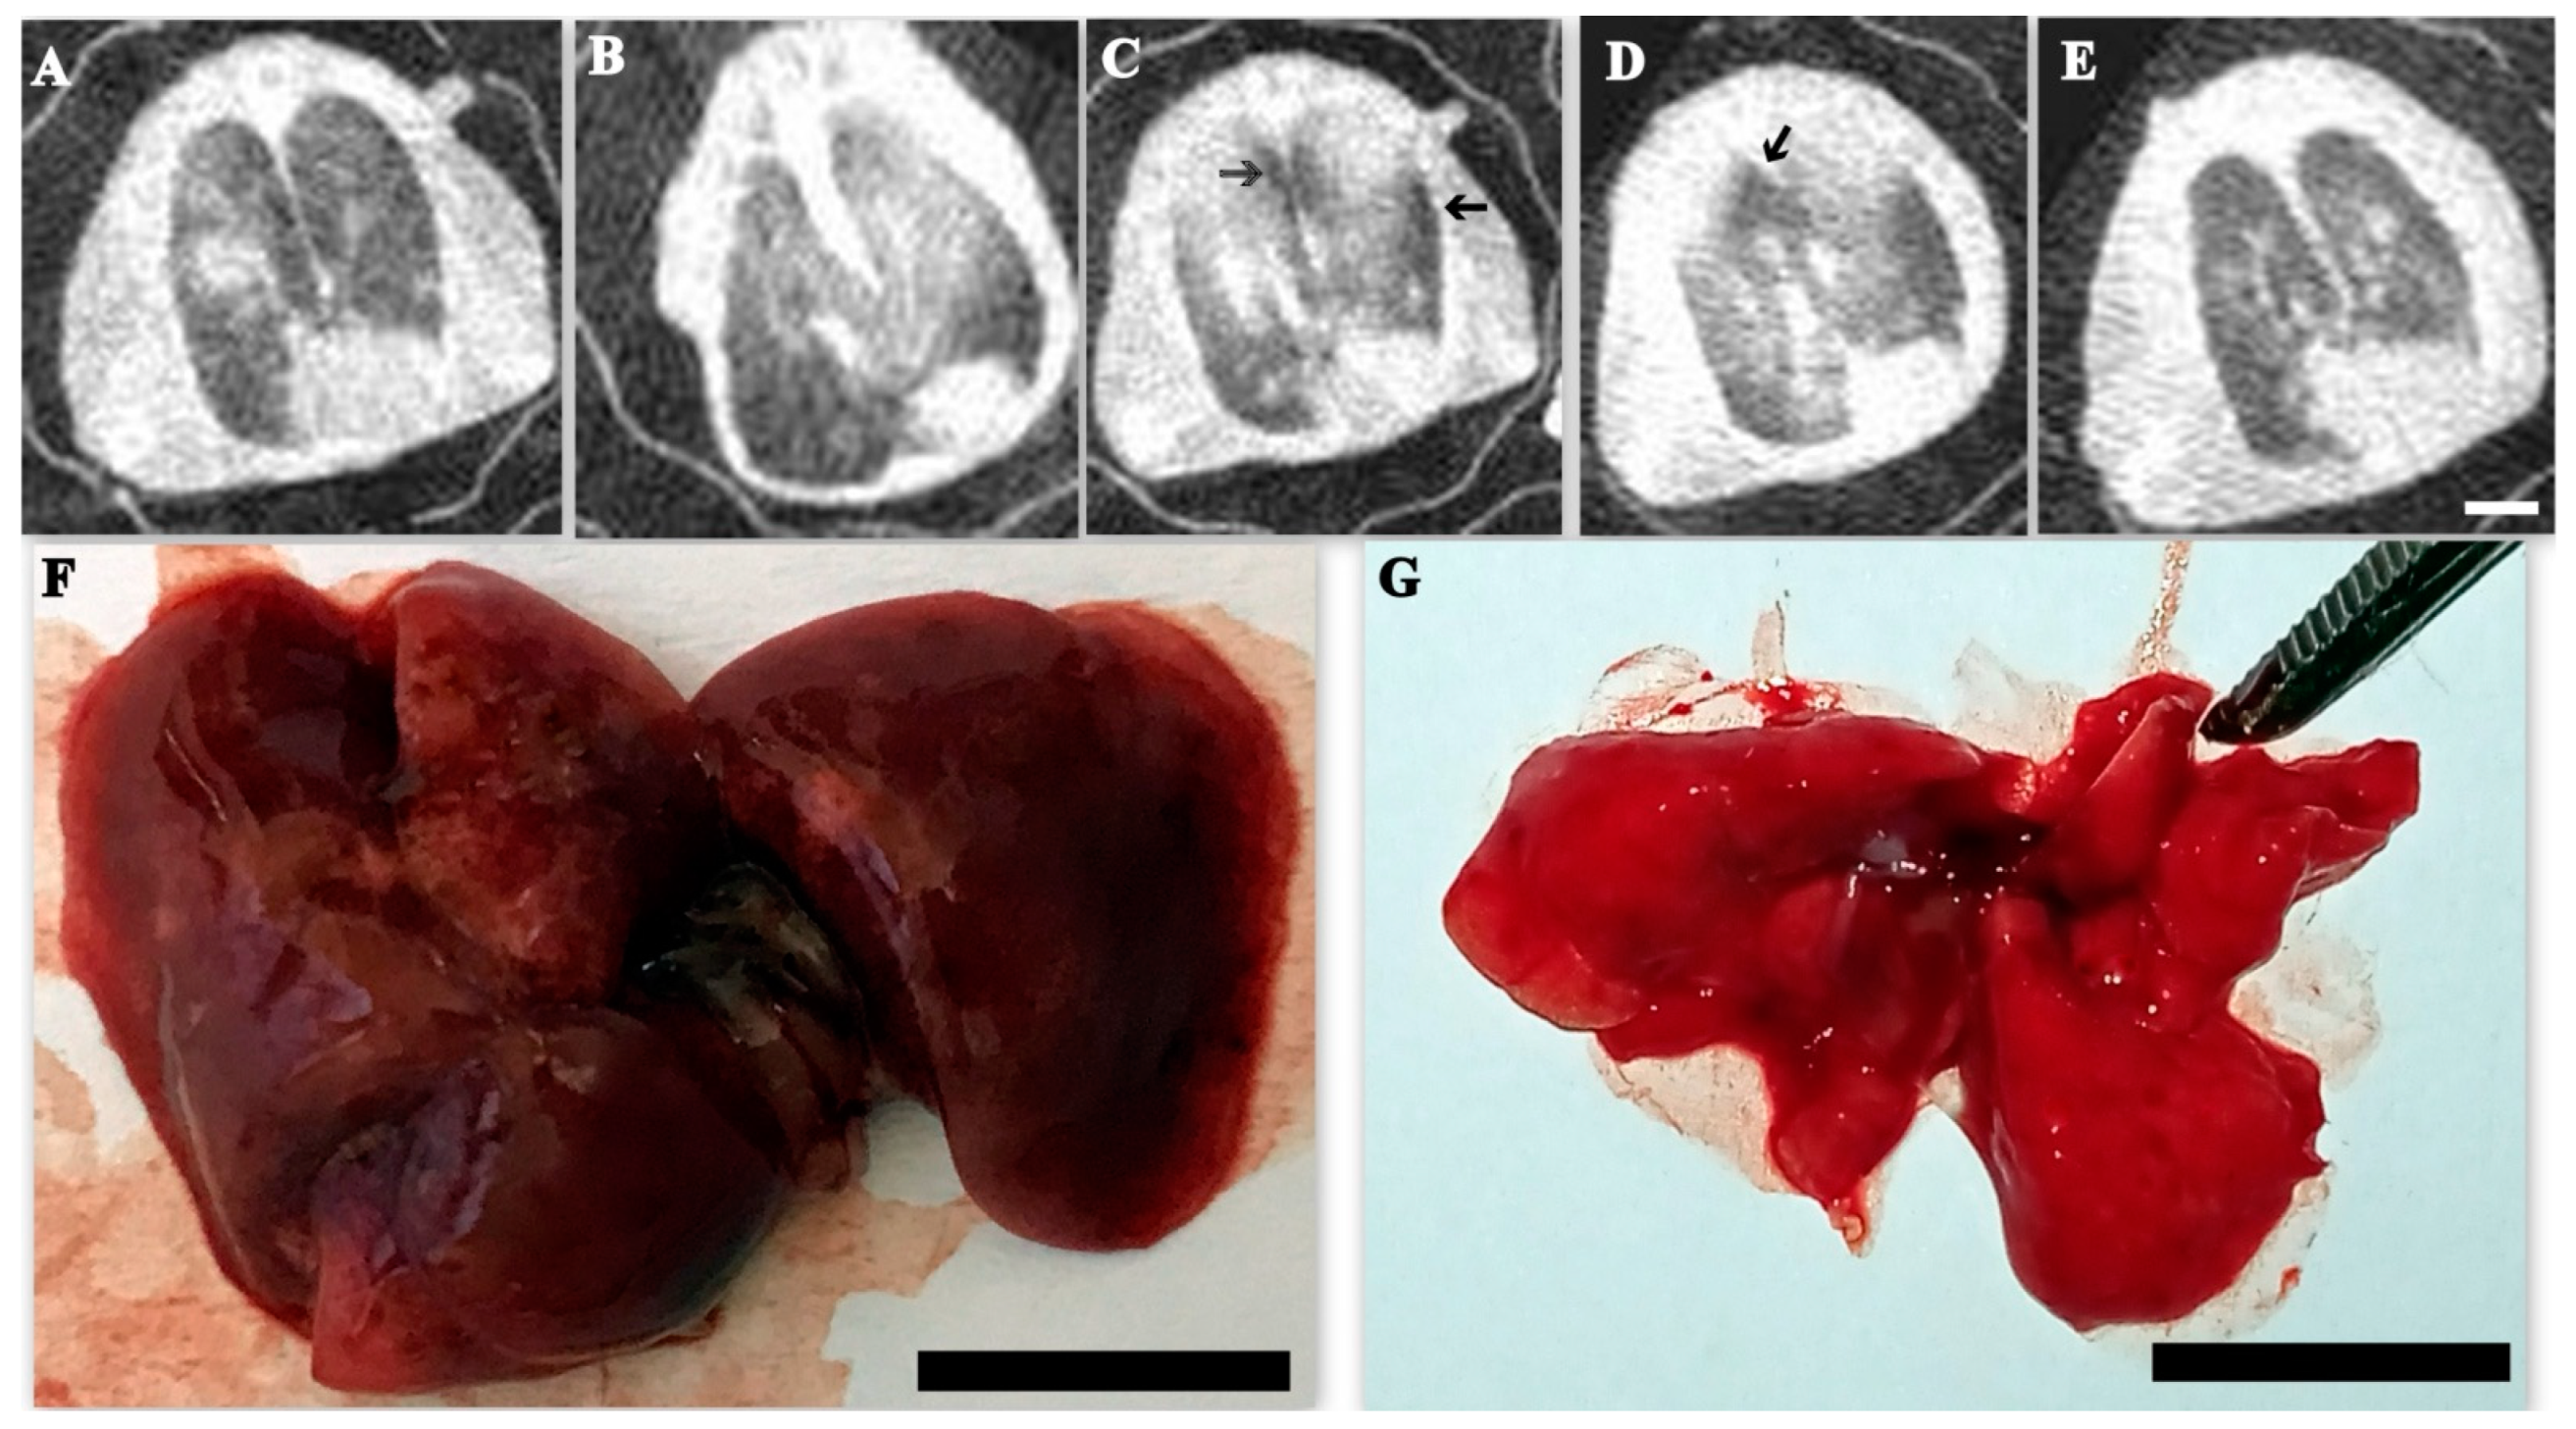

3.8. Lung Computed Tomography and Gross Pathology